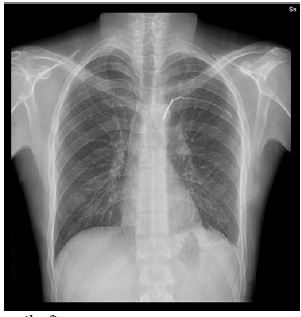

Figure 3: Chest X-ray performed one month after surgery.

The patient was discharged in good general condition; chest X-ray performed one month after surgery did not disclose any pathologic finding (Figure 3).